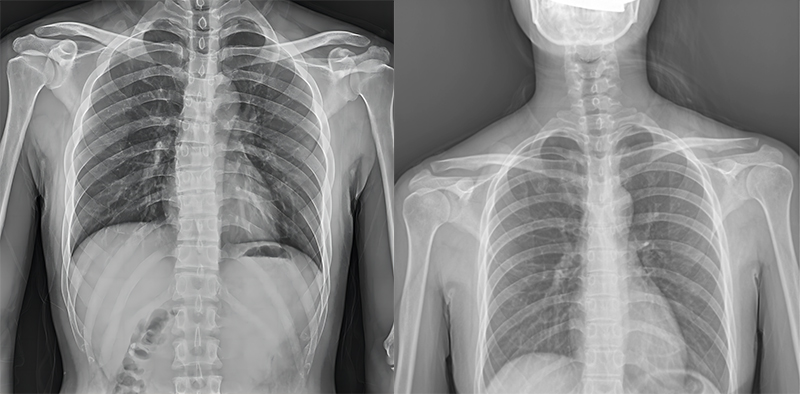

百微米DR與普通像素尺寸DR的影像對比

以胸部攝影為例,通過對比百微米大平板與普通像素尺寸平板的影像,可以看到百微米影像對比度適中,圖像清晰度更高,成像細節(jié)更加豐富。在胸部影像顯示中肺門影結構、肺紋理等細節(jié)展示更清楚,兩側膈肌邊緣、心臟、縱隔邊緣清晰銳利顯示,在影像中都可以清晰地顯示胸部細微結構,滿足臨床診斷要求。